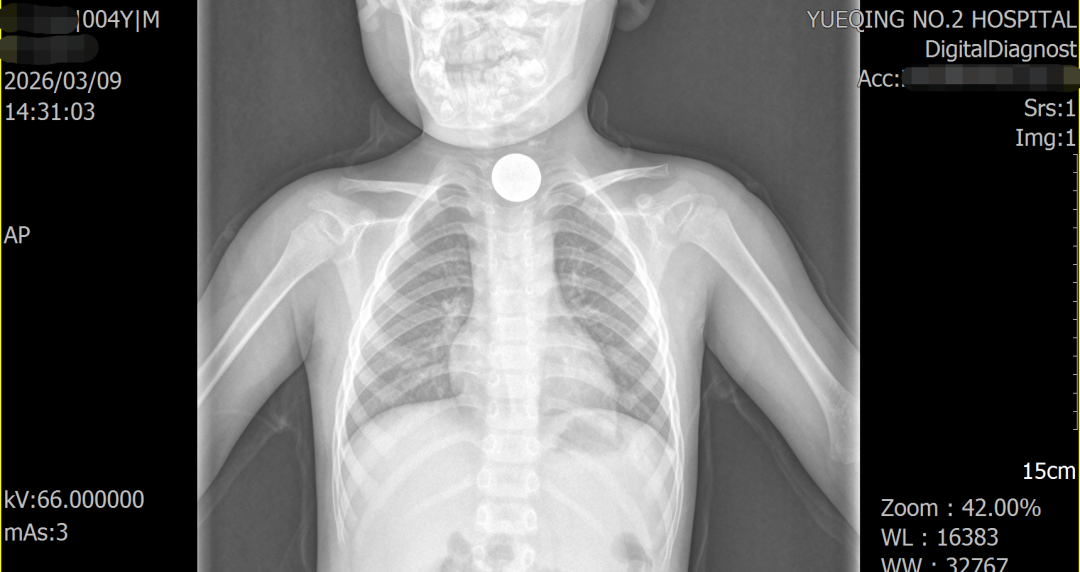

事情的起因,是小宝突然指着胸口告诉妈妈身体不舒服。起初家长以为只是孩子撒娇,可在孩子反复诉说不适后,家人立刻带他前往乐清市二医检查。一张 X 光片,让所有人的心都揪了起来 —— 小宝的食道入口处,清晰可见一枚一元硬币。家人仔细回忆才想起,这枚硬币大概率是孩子两个月前玩耍时不慎吞下的,当时孩子只有短暂哭闹、食欲变差,没多久就恢复正常,谁也没料到,硬币竟悄悄卡在了食管里。

第二天一早,各项诊疗准备全部就绪。可刚进入诊疗间,小宝就因对陌生环境感到害怕,大声哭了起来。医护人员见状立刻蹲下身,用温柔的话语耐心安抚孩子:“宝贝最勇敢啦,阿姨准备了小奖励,等你睡醒就能拿到。”“你看这个面罩,像不像太空人的小面具?戴上我们一起去太空探险。” 在医护人员的温柔引导下,小宝的情绪渐渐平复下来。随后,麻醉团队精准给药,孩子很快安静进入睡眠状态,全程没有挣扎、没有恐惧。内镜顺利进入食管,屏幕上清晰显示出一枚已经氧化发黑的硬币,其周边的食管黏膜也出现了充血水肿的情况。内镜医生与护士沉着冷静、默契配合,操控器械精准夹住硬币边缘,轻柔调整角度,顺着食管的生理弧度平稳外退。仅仅两分钟,这枚在孩子食管里 “潜伏” 两个多月的硬币就被完整取出,检查发现孩子食管黏膜仅轻微损伤,无穿孔、无出血,操作间里的所有人都松了一口气。此时小宝还在安稳熟睡,全然不知一场惊险的 “救援” 已顺利完成。当门外的妈妈看到被取出的硬币时,瞬间红了眼眶,不停向医护人员道谢:“太感谢你们了,要是一直不知道,真的不敢想后果……”